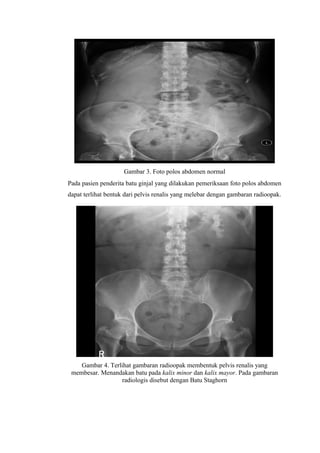

Gambaran USG pada gambar 8. Menunjukan pelvis yang membesar karena

hambatan aliran urin akibat adanya nefrolithiasis sehingga terjadi hidronefrosis.

Pada batu ureter dapat ditemukan adanya hidroureter akibat adanya sumbatan

pada ureter. Dapat juga ditemukan acoustic shadow dan adanya twinkling artefact.

Gambar 12. Tampak hiperechoic pada batu di ureter dengan adanya acoustic

shadow dan adanya twingkling artefacts (Mos et al, 2010)

Twninkling artefact atau color comet tail artefact adalah gambaran pada USG

Doppler akibat adanya gambaran pergerakan yang palsu, biasanya karena

gambaran di USG Doppler dengan opasitas yang tinggi, biasanya disebabkan oleh

batu (Hircs et al, 2011).